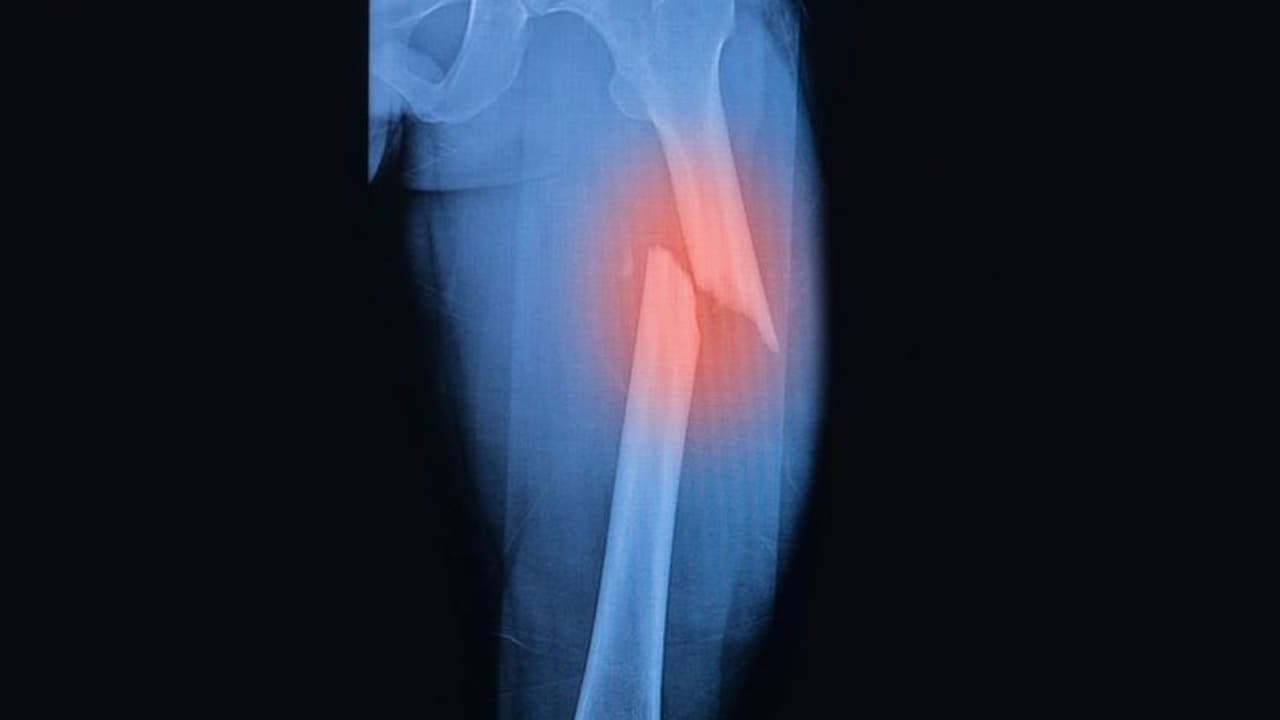

ಮೂಳೆ ಮುರಿತದ ಬಗ್ಗೆ ವೈದ್ಯರು ಸಂಶೋಧನೆ ನಡೆಸಿದ್ದು, ಸಾಮಾನ್ಯವಾಗಿ ವಯಸ್ಸಾದವರಿಗೆ ಹಾಗೂ ಕಾಯಿಲೆ ಇರುವರು ಮೂಳೆ ನೋವಿನಿಂದ ಬಳಲುತ್ತಾರೆ. ಈ ಸಮಸ್ಯೆ ವಯಸ್ಕರಲ್ಲಿಯೇ ಏಕೆ ಎಂದು ಪತ್ತೆ ಹಚ್ಚಲು ಸಂಶೋಧನೆ ನಡೆಸಲಾಗಿತ್ತು.

ನಾಲ್ಕು ಸಾವಿರ ಜನರನ್ನು ಈ ಸಂಶೋಧನಗೆ ಬಳಸಲಾಗಿತ್ತು. ಪ್ರತಿ ವರ್ಷ ಶೇ. 0.89 -ಶೇ.0.70 ಮಂದಿ ವಿವಿಧ ನೋವಿನಿಂದ ಬಳಲುತ್ತಿದ್ದರು. ಅದರಲ್ಲಿ ಶೇ.0.66 ಮಂದಿ ಒಂದಲ್ಲ ಒಂದು ಕಾಲದಲ್ಲಿ ಮೂಳೆಗೆ ಏಟು ತಿಂದವರೇ ಆಗಿದ್ದರು.

ಯಾವುದೇ ಮೂಳೆಗೆ ಹಾನಿಯಾದರೂ ಮೊದಲೆರಡು ವರ್ಷಗಳು ಎಲುಬಿನ ಸಾಂದ್ರತೆ ಕಡಿಮೆಯಾಗುತ್ತದೆ. ಇದು ಮಂಡಿ ನೋವು, ಭುಜ ನೋವು...ಹೀಗೆ ದೇಹದ ವಿವಿಧ ನೋವಿಗೆ ದಾರಿಗೆ ಮಾಡಿ ಕೊಡುತ್ತದೆ. ಯಾವಾಗಲೋ ತಿಂದ ಏಟು, ಇನ್ಯಾವುದೋ ಸಮಯದಲ್ಲಿ ಮನುಷ್ಯನನ್ನು ಕಾಡುತ್ತದೆ.

ಎಲುಬಿನ ಸಾಂದ್ರತೆ ಕಡಿಯಾಗುವುದರಿಂದ ರಕ್ತದಲ್ಲಿ ಉರಿಯಾಗುತ್ತದೆ. ಚಿಕ್ಕ ಮೂಳೆಗಾಗುವ ಪೆಟ್ಟನ್ನು ಚಿಕಿತ್ಸೆ ಮೂಲಕ ಸರಿಪಡಿಸಬಹುದಾಗಿದ್ದು, ವಯಸ್ಸಾಗುತ್ತಿದ್ದಂತೆ ಅದರ ಸುತ್ತ ಇರುವ ಮೂಳೆ ನೋವೂ ಶುರುವಾಗುತ್ತದೆ.